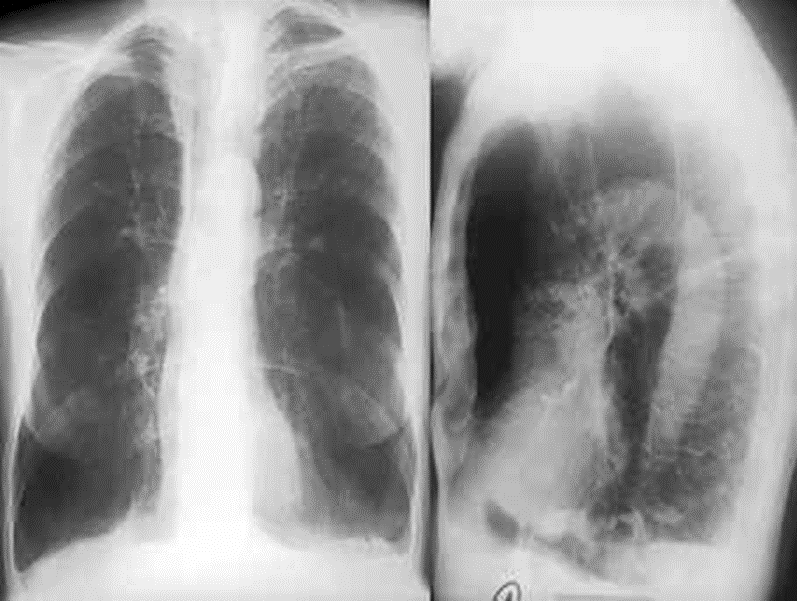

(2)慢性阻塞性肺疾病:回到导课时那个COPD患者,分析为什么能够判断出他是COPD患者,分析其体征,并复习前面体格检查中为什么会出现对应的视触叩听异常结果。(6min)

(3)支气管哮喘:首先讲解哮喘和COPD的不同;准备一张哮喘患者急性发作期的X线片,讲解哮喘的体征。结合一个支气管结核误诊为哮喘的病例,说明哮喘的体格检查体征改变,并复习不同的干啰音的差别。(4min)